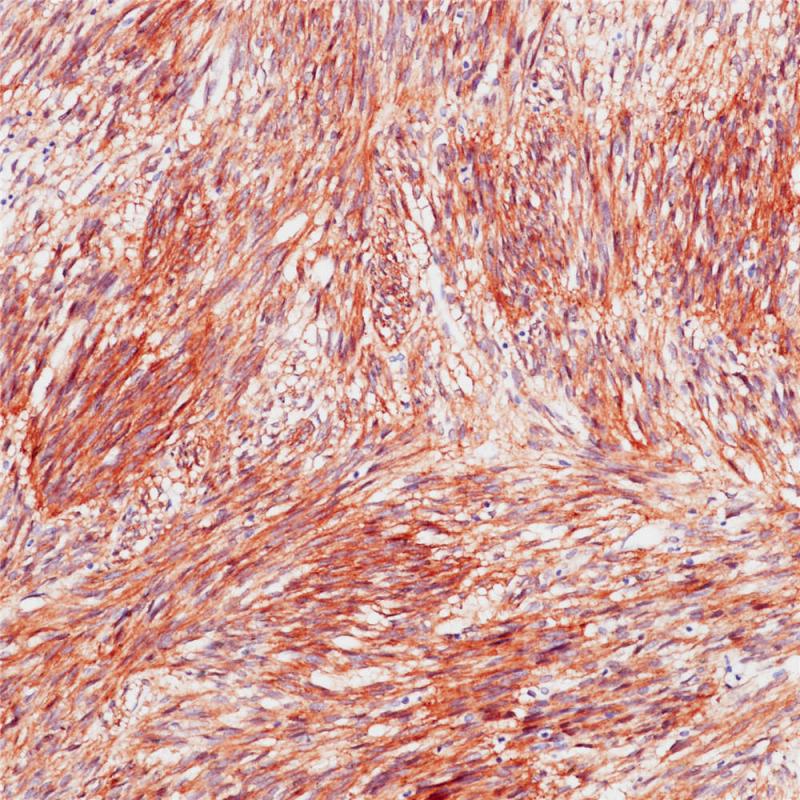

DOG1是由TMEM16A基因编码的钙离子依赖性的氯离子通道蛋白,定位于染色体11q13。DOG1具有调节胃肠道平滑肌的胆碱能活性以及细胞的存活及增殖功能。超过90%的胃肠道间质瘤(GISTs)是DOG1阳性,染色定位为细胞质和细胞膜,呈弥漫性密集强染色。DOG1与CD117在GIST的鉴定中可作为重要指标,DOG1的灵敏度及特异性高于CD117。DOG1也用于唾液腺癌以及胰腺、肾脏癌鉴定中。

阳性对照

胃肠道间质瘤

亚细胞定位

细胞膜/细胞质